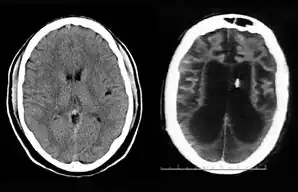

Left: CT scan of normal brain; Right: Schiavo's 2002 CT scan provided by Ronald Cranford, showing loss of brain tissue. The black area is liquid, indicating hydrocephalus ex vacuo.[36] The small white piece in the right image is the thalamic stimulator implanted in her brain.

On August 10, 2001, on remand from the Florida Second District Court of Appeal, Judge Greer heard a motion from the Schindlers claiming that new medical treatment could restore sufficient cognitive ability such that Terri Schiavo herself would be able to decide to continue life-prolonging measures. The court also heard motions from the Schindlers to remove the guardian (Michael Schiavo) and to require Judge Greer to recuse himself. Judge Greer denied the motions and the Schindlers appealed to the Second District Court of Appeals. On October 17, 2001, the Court of Appeal affirmed the denials of the motions to remove and recuse. The Court of Appeals acknowledged that their opinion misled the trial court, and they remanded the question of Terri Schiavo's wishes back to the trial court and required an evidentiary hearing to be held. The court specified that five board certified neurologists were to testify. The Schindlers were allowed to choose two doctors to present findings at an evidentiary hearing while Schiavo could introduce two rebuttal experts. Finally, the trial court itself would appoint a new independent physician to examine and evaluate Terri Schiavo's condition. These decisions, all published in a single order by the Florida Second District Court of Appeal,[37] came to be known by the court as Schiavo III in its later rulings. In October 2002, on remand by the Second District Court of Appeal, an evidentiary hearing was held in Judge Greer's court to determine whether new therapy treatments could help Terri Schiavo restore any cognitive function. In preparation for the trial, a new computed axial tomography scan (CAT scan) was performed, which showed severe cerebral atrophy. An EEG showed no measurable brain activity. The five physicians chosen were William Maxfield, a radiologist, and four neurologists: William Hammesfahr, Ronald Cranford, Melvin Greer and Peter Bambakidis.[38]

The five doctors examined Terri Schiavo's medical records, brain scans, the videos, and Terri herself. Cranford, Greer, and Bambakidis testified that Terri Schiavo was in a persistent vegetative state (PVS). Maxfield and Hammesfahr testified that she was in a minimally conscious state. As part of the court-ordered medical exam, six hours of video of Terri Schiavo were taped and filed at the Pinellas County courthouse. The tape included Terri Schiavo with her mother and neurologist William Hammesfahr. The entire tape was viewed by Judge Greer, who wrote, Terri "clearly does not consistently respond to her mother". From that six hours of video, the Schindlers and their supporters produced six video clips intended to support their case, totaling less than six minutes, and released those clips to public websites.[1] Judge Greer ruled that Terri Schiavo was in a PVS, and was beyond hope of significant improvement. The trial court order was particularly critical of Hammesfahr's testimony, which claimed positive results in similar cases by use of vasodilation therapy, the success of which is unsupported in the medical literature.[39] This ruling was later affirmed by Florida's Second District Court of Appeal, which stated that "this court has closely examined all of the evidence in the record", and "we have ... carefully observed the video tapes in their entirety." The court concluded that "if we were called upon to review the guardianship court's decision de novo, we would still affirm it." This decision by the Second District Court of Appeals[40] came to be known as Schiavo IV in later rulings.